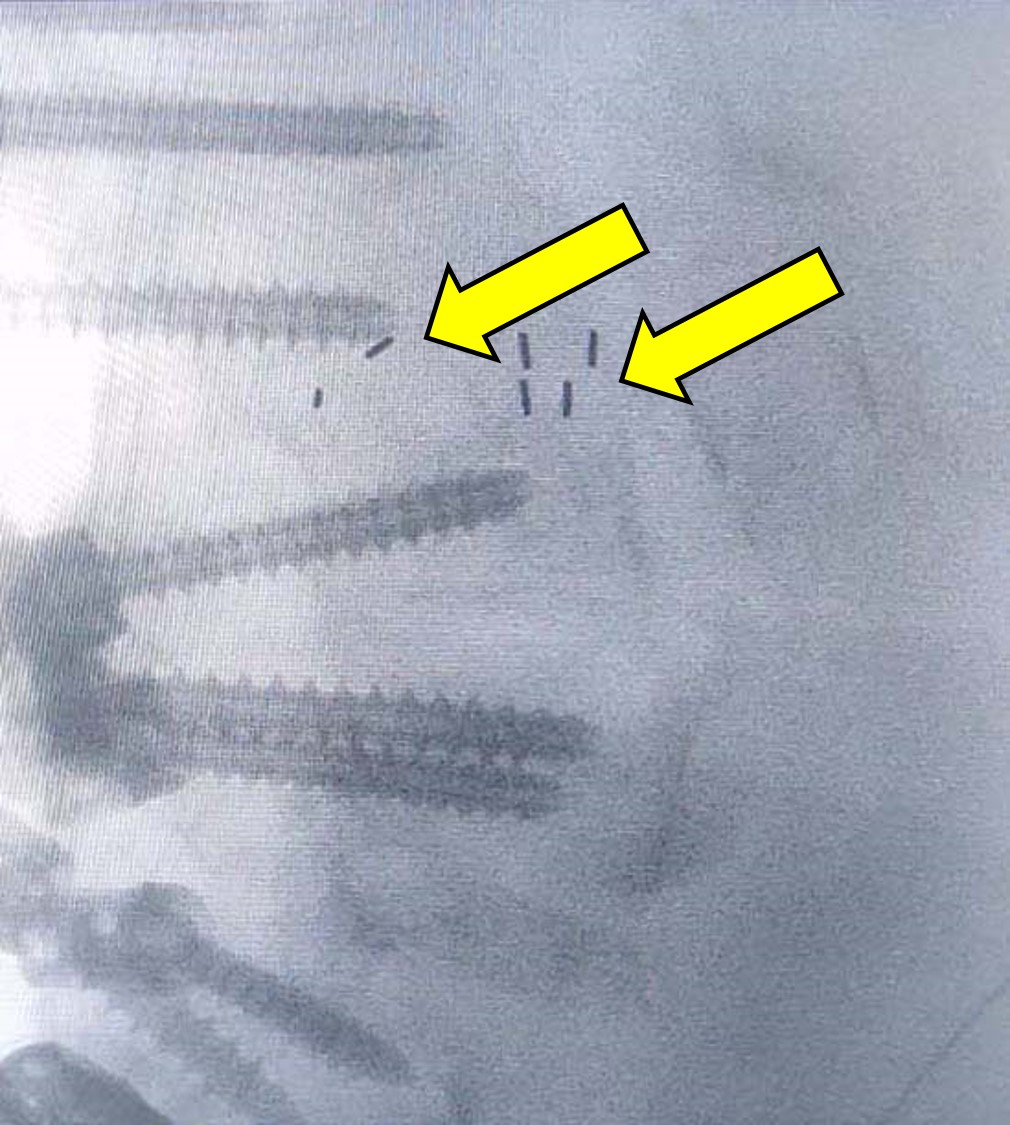

Εικόνα 3

α. Προσθιοπισθία (Face) ακτινογραφία Σπονδυλικής Στήλη σε όρθια στάση. Παρατηρείται ότι η σπονδυλοδεσία εκτείνεται από τον 10ο θωρακικό σπόνδυλο μέχρι το ιερό οστούν κα τα λαγόνια αμφοτεροπλεύρως. Με σχετική δυσκολία λόγω της ποιότητας της ακτινογραφίας, διαπιστώνεται θραύση της αριστερής ράβδου πάνω από τη βίδα που έχει τοποθετηθεί στον 5ο οσφυϊκό σπόνδυλο.

β. Προσθιοπισθία ακτινογραφία Εικονίζονται οι βίδες (κοχλίες) που έχουν τοποθετηθεί στις λαγόνιες ακρολοφίες.

γ. Πλάγια (Profil) ακτινογραφία της Σπονδυλικής Στήλης Παρατηρείται ότι υφίσταται μεγάλη κύρτωση προς τα εμπρός της Θωρακικής Μοίρας της Σπονδυλικής Στήλης πάνω από την περιοχή της σπονδυλοδεσίας και η οσφυϊκή λόρδωση είναι πολύ μικρή. Ο άξονας του κέντρου βάρους του σώματος είναι πολύ μπροστά από το πρόσθιο άκρο του 3ου οσφυϊκού και του 1ου ιερού σπονδύλου.